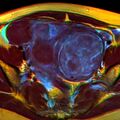

A very large (9 cm) fibroid of the uterus which is causing pelvic congestion syndrome as seen on CT

A very large (9 cm) fibroid of the uterus which is causing pelvic congestion syndrome as seen on ultrasound